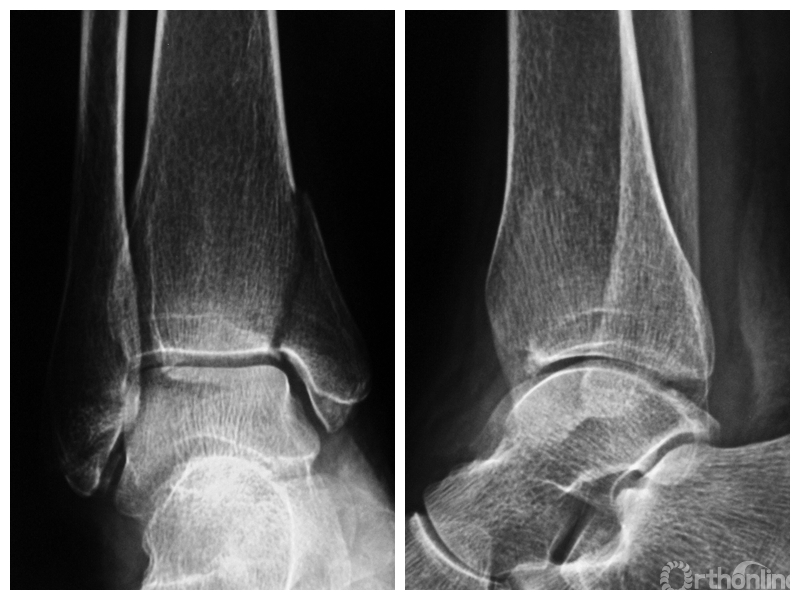

图1 支撑钢板固定组患者,女,63岁,右侧旋后-内收型II度踝关节骨折 a. 术前正侧位X线片;b. 术前CT;c. 术后2周正侧位X线片;d. 术后2年正侧位X线片

图1a 术前正侧位X线片